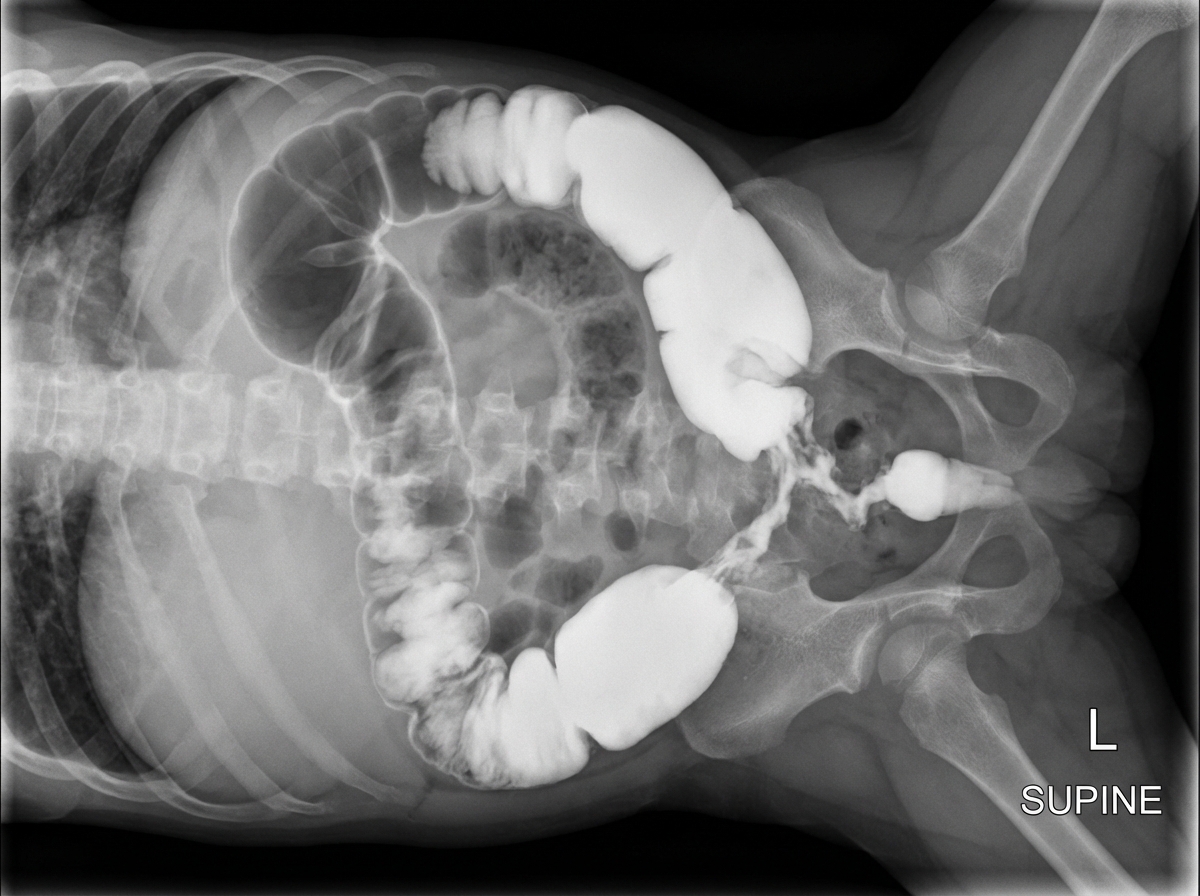

A 5-day-old term male neonate presents with delayed passage of meconium, abdominal distension, and bilious vomiting. Barium enema and intestinal biopsy findings are shown. What is the diagnosis?

Explanation: ***Congenital aganglionic megacolon*** - **Delayed meconium passage** beyond 48 hours, **abdominal distension**, and **bilious vomiting** in a neonate are classic signs of **Hirschsprung's disease**. - **Barium enema** shows characteristic **transition zone** between dilated proximal colon and narrow distal segment, while **rectal biopsy** confirms **absence of ganglion cells** in the myenteric plexus. *Hypertrophic pyloric stenosis* - Presents with **non-bilious projectile vomiting** typically at 2-8 weeks of age, not in the first few days of life. - Associated with **palpable olive-shaped mass** in the epigastrium and **gastric outlet obstruction**, not colonic obstruction with delayed meconium passage. *Cystic fibrosis* - Can cause **meconium ileus** in newborns, but this involves **small bowel obstruction** with thick, inspissated meconium in the terminal ileum. - **Barium enema** would show **microcolon** and **soap bubble sign** in the right lower quadrant, not the transition zone seen in Hirschsprung's disease. *Intestinal malrotation* - Presents with **bilious vomiting** due to **midgut volvulus**, but typically occurs within the first few weeks to months of life. - **Upper GI series** would show **duodenal obstruction** with **corkscrew appearance** of the small bowel, and **rectal biopsy** would be normal with ganglion cells present.